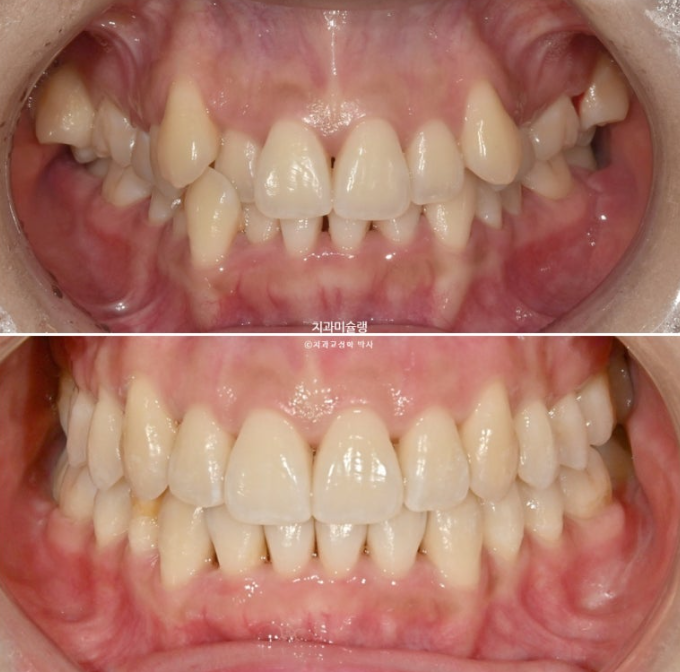

2년 전 덧니 교정치료를 위해 내원한 환자분입니다.

중심선 문제, 블랙트라이앵글, 과개교합, 반대교합, 가위교합 등이 보입니다.

발견되는 부정교합의 종류들을 나열해보자면

중심선 불일치

과개교합

대구치 가위교합

심한 덧니

전치부 반대교합

부정교합은 아니지만 블랙트라이앵글

정도가 되겠습니다.

이 정도라면 작은어금니 4개 발치교정 진단을 할만도 하지만

입술 돌출이 없고 입술이 얇아 발치교정이 고민되는 상황입니다.

결국 환자분과 논의 후 입매 변화 없는 비발치로 진행하기로 합니다.

중심선의 개선, 과개교합의 개선, 덧니의 개선, 블랙트라이앵글의 개선이 보입니다.

23.08~25.10

앞니는 뒤로 들어가지도, 나오지도 않고 잘 유지되었습니다.